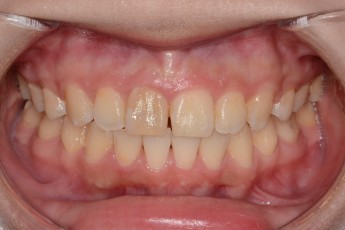

Before

After